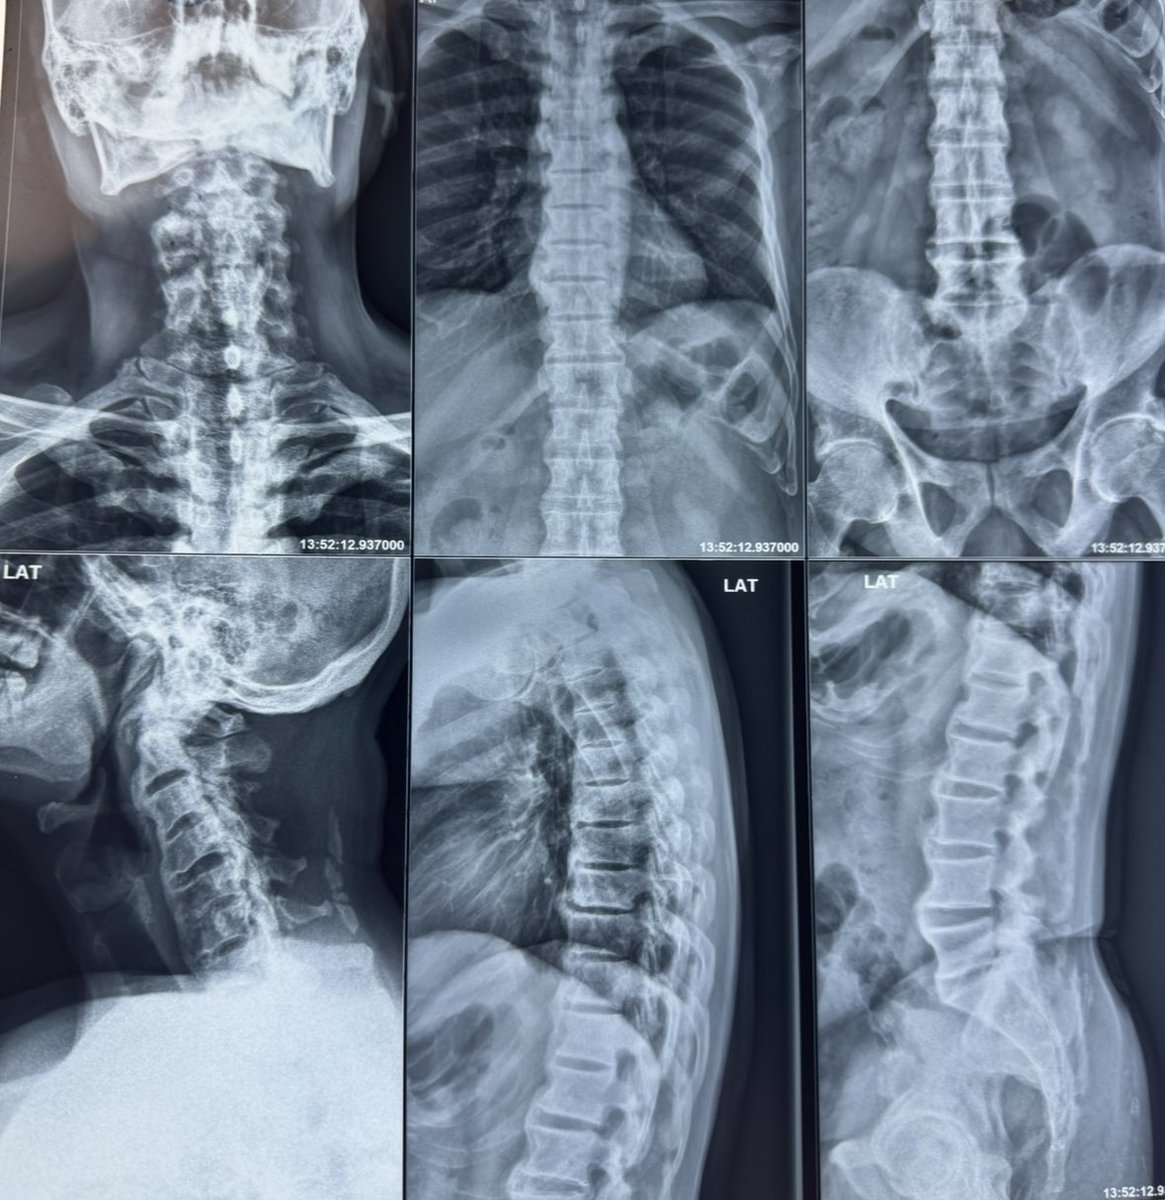

This patient presented with neck pain.

What is your diagnosis?

Comment below.👇